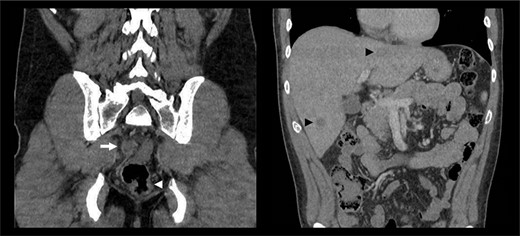

A 39-year-old man presented to the emergency department with a one-day history of right upper quadrant and several weeks of fluctuating tenesmus and diarrhoea on a background of HIV infection and previous bacterial sexually transmitted infections. The patient identified as homosexual and reported previous intravenous drug use with methamphetamine. There was no history of viral hepatitis and immunizations were up to date. Examination demonstrated a tender right upper quadrant without peritonism. Blood investigations were non-specific, showing an isolated elevation of C-reactive protein to 69 mg/l, with normal white cell count, lipase and liver function enzymes. Serological studies were negative for Chlamydia and Gonorrhoea species and confirmed an undetectable viral load of HIV RNA. Faeces and urine cultures did not isolate any organisms. A CT abdomen-pelvis with intravenous contrast was performed, demonstrating short segment irregular rectal wall thickening, bilateral mesorectal lymphadenopathy and multiple hypoattenuating liver lesions—an overall appearance highly suspicious for metastatic rectal cancer (Fig. 1).

CT abdomen-pelvis with intravenous contrast demonstrating rectal wall irregularity (white arrowhead), bulky mesorectal lymphadenopathy (white arrow) and multiple hypoattenuating liver lesions (black arrow heads).